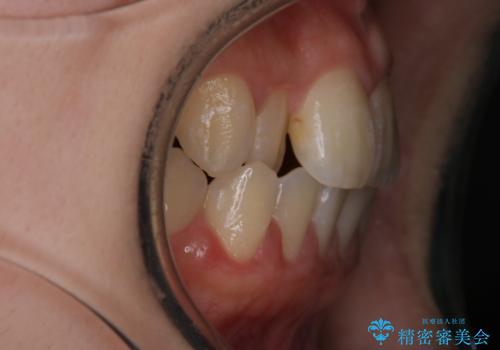

- 前歯の叢生を主訴に来院されました。目立たない装置を希望されたためインビザラインで治療を行いました。

IPRと拡大をし、叢生を治しました。右上2番は反対咬合でしたが短期間できれいに治りました。